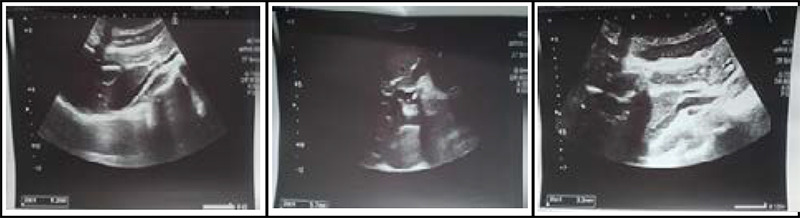

胆总管十二指肠瘘是胆总管与十二指肠之间的异常连接。最常见的原因是胆囊结石,然而,其他原因是医源性因素,胆管结石(胆总管结石),和慢性十二指肠溃疡。在此,我们报告一例胆囊切除术后继发于长期胆总管结石的胆总管十二指肠瘘,在过去的三年里,他表现出间歇性腹痛,并在内镜下逆行胆管造影时发现胆总管十二指肠瘘。由于患者复发性疼痛并伴有胆总管结石,需要手术治疗。胆管炎复发疑为胆总管十二指肠瘘,难治性和复杂性病例建议手术治疗。对于较大的瘘管,尤其是无法解决的药物治疗,也建议手术治疗。本病例强调胆总管结石合并胆总管十二指肠瘘的治疗选择。

Choledochoduodenal fistula is an abnormal connection between the common bile duct and the duodenum. The commonest cause is cholecystolithiasis, however, other causes are iatrogenic factors, bile duct stones (choledocholithiasis), and chronic duodenal ulcers. Here, we report a case of choledochoduodenal fistula secondary to long standing choledocholithiasis post cholecystectomy who presented with intermittent abdominal pain in the past three years which revealed choledochoduodenal fistula during Endoscopic Retrograde Cholangiopancreatography. As the patient had recurrent pain along with choledocholithiasis, surgical intervention was indicated. Choledochoduodenal fistula is suspected in case of recurrent cholangitis and surgery is recommended for refractory and complicated cases. Surgical treatment is also recommended for larger fistulas and especially with non-resolving medical treatment. This case highlights the treatment option for choledocholithiasis with choledochoduodenal fistula.